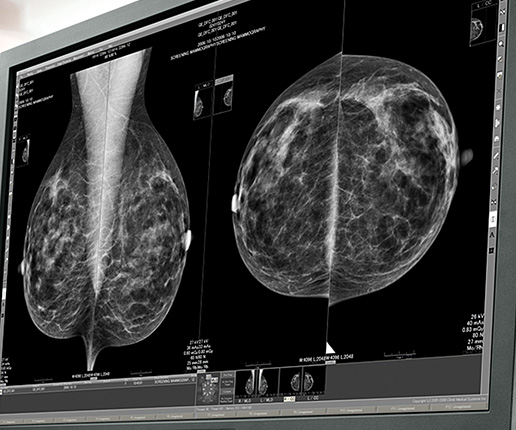

Na czym polega tomosynteza w mammografii? W obrazach z tomosyntezą, w porównaniu do obrazów z kompleksową superpozycją wszystkich struktur w piersi (charakterystyczną dla tradycyjnych mammografów 2D), lekarz radiolog może identyfikować poszczególne struktury, eliminując jednocześnie problem wynikający z nakładania się ich na siebie (mammografy 2D). Podczas skanowania z tomosyntezą, wykonywana jest seria zdjęć piersi pod różnymi kątami. Obrazy te są następnie użyte do wygenerowania serii cienkich (1-milimetrowych)…